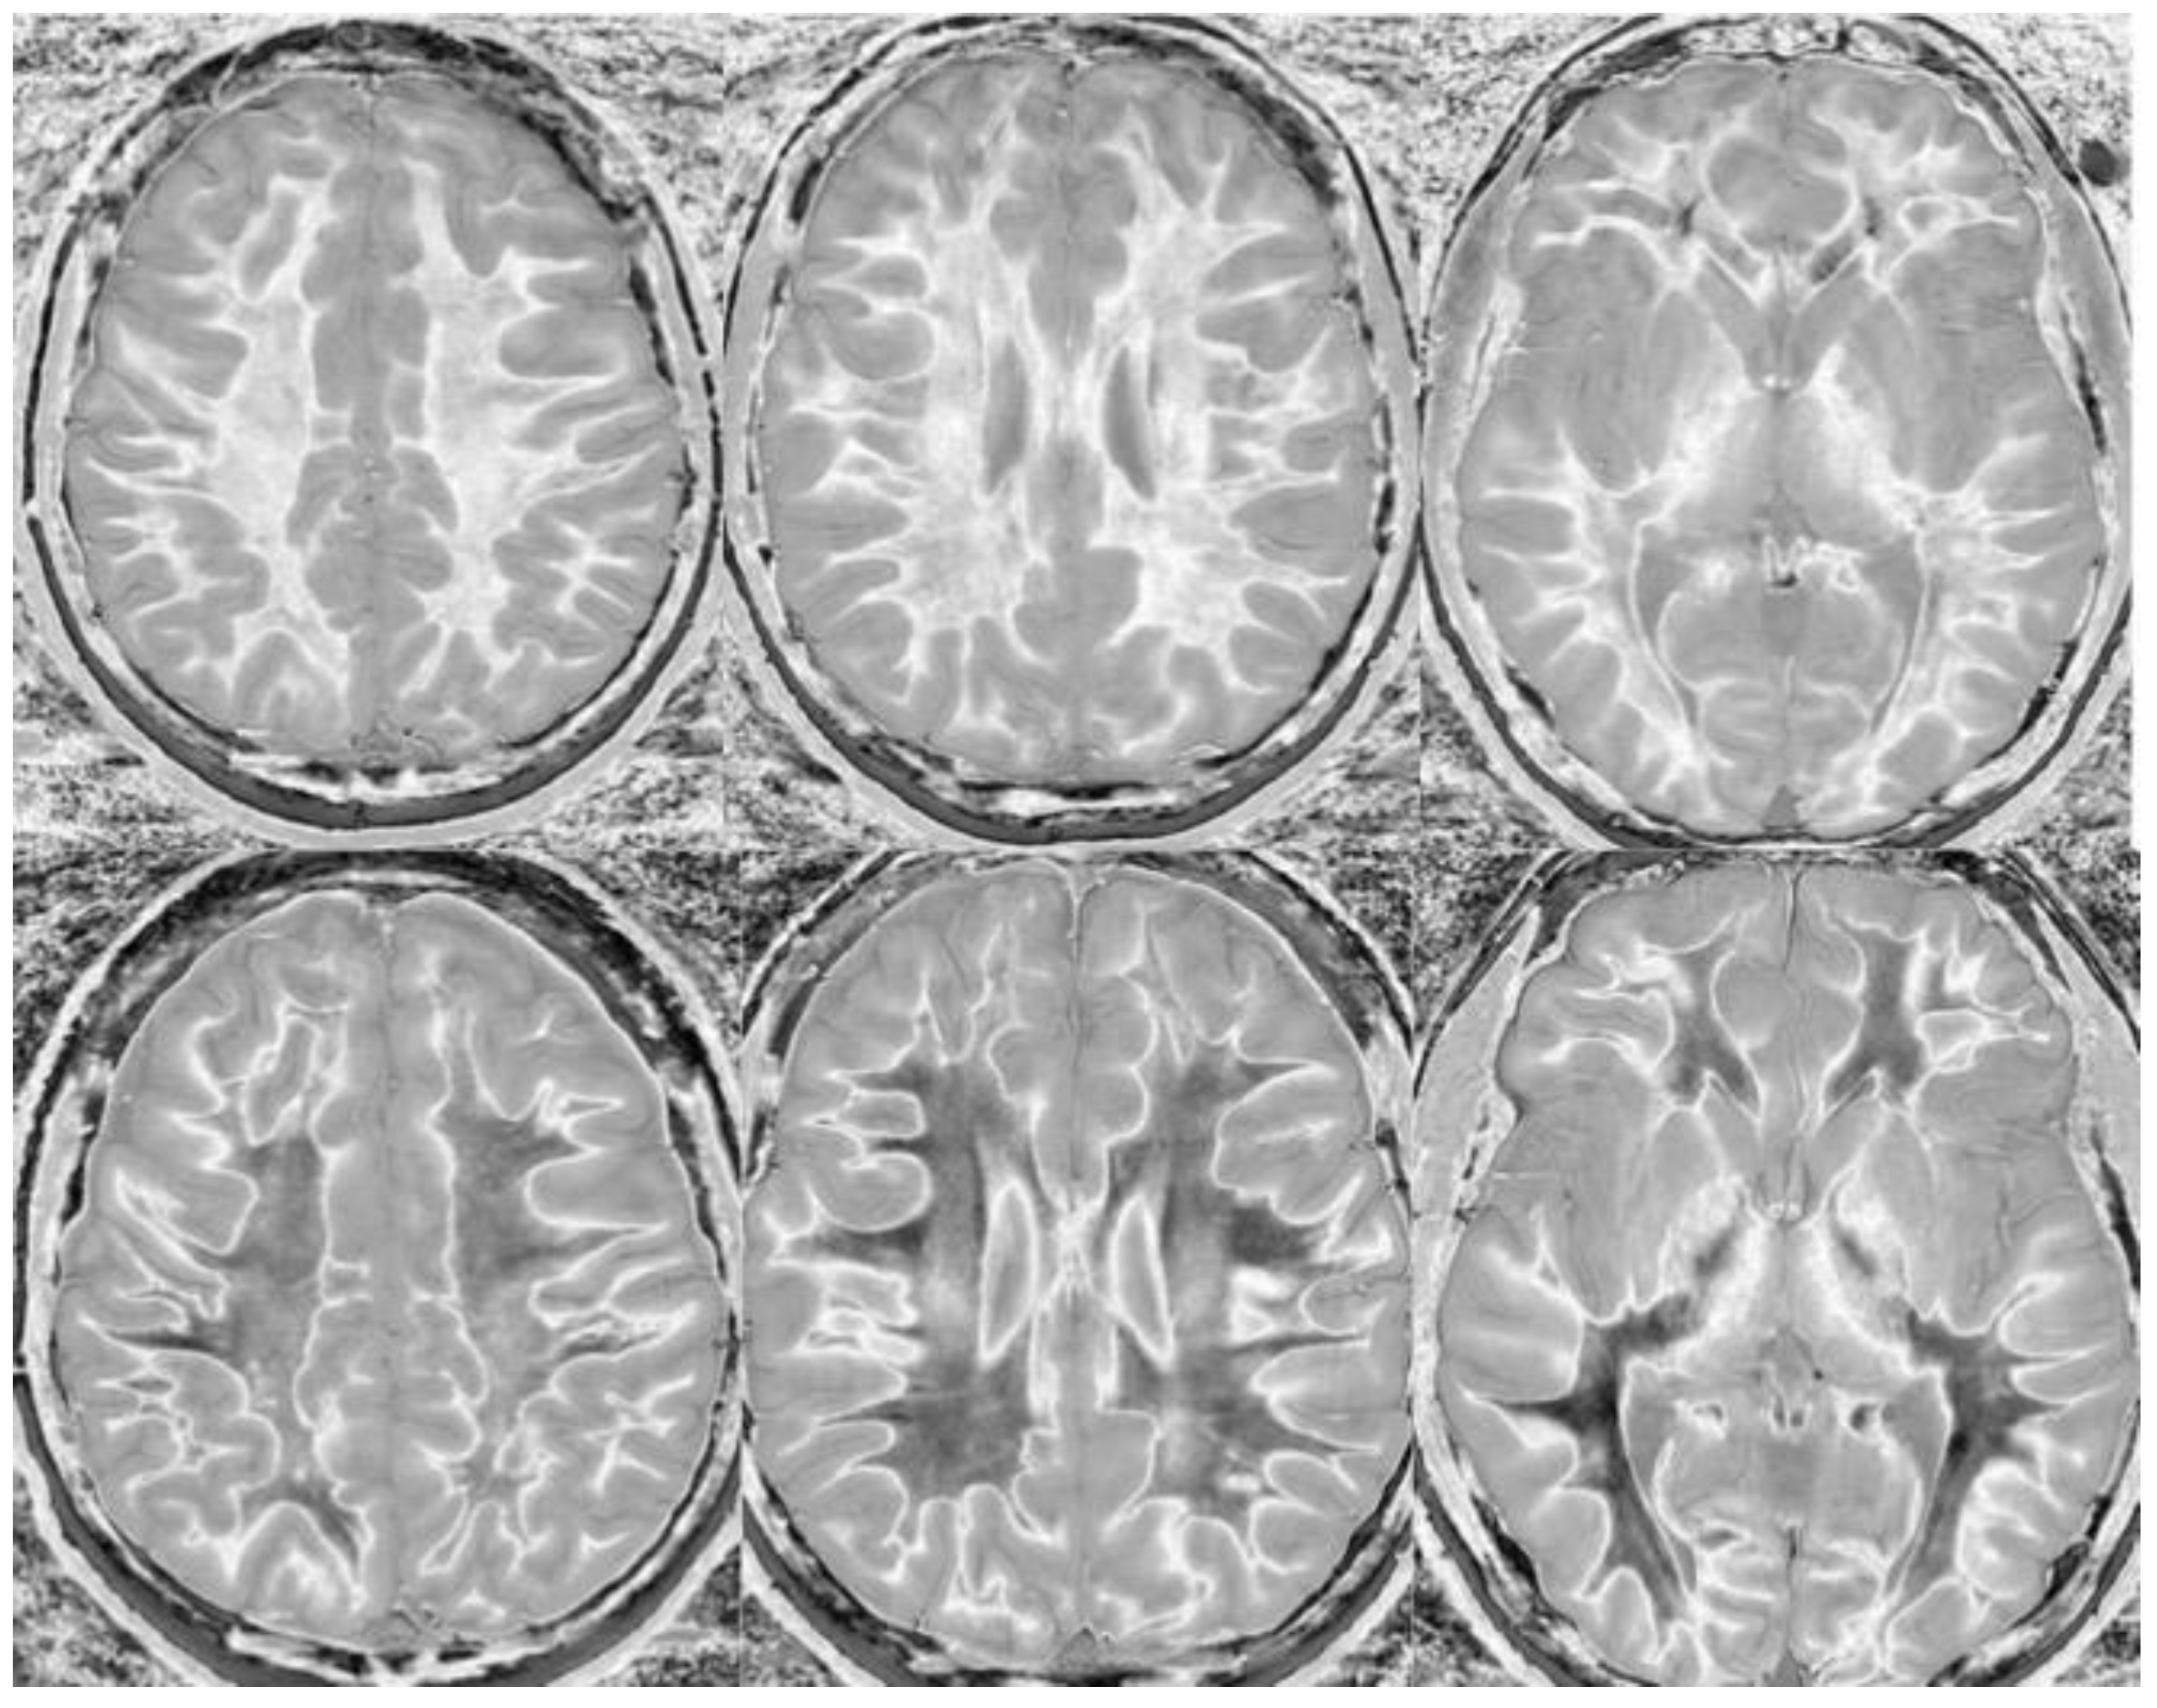

Figure 14.

Normal and abnormal divided Subtracted Inversion Recovery (dSIR) images. Narrow middle domain images in three patients at the level of the centrum semiovale. TIshort = 350 ms. TIlong = 500 ms. TE = 7 ms, TR = 5000 ms. The left image shows an example of the “white out sign”, with a diffusely increased signal throughout the white matter. The center image is an example of normal. The white matter has a mildly increased signal that is normal because TIshort = 350 ms nulls tissue with T1 values less than that of white matter. The image on the right has an intermediate appearance, probably abnormal but not a “white out”.